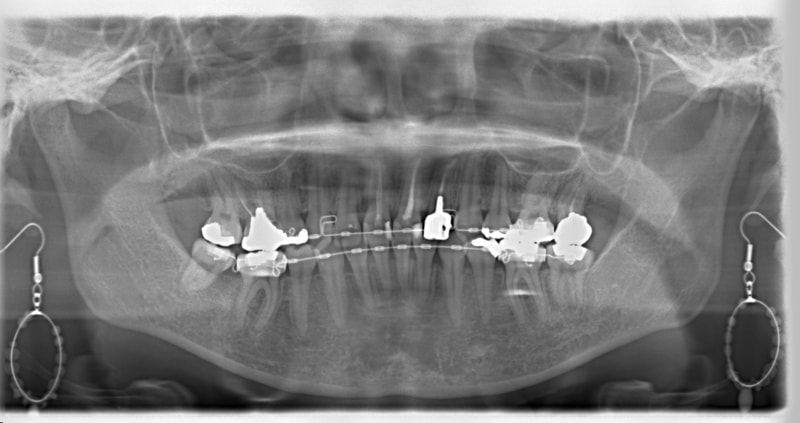

治療後(3年2ヶ月後)

治療開始から1年8ヶ月後